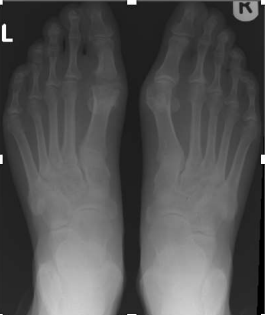

Figure 1

Figure 2

Figure 3

Radiographic evaluation revealed a preoperative mean hallux valgus angle (HVA) of 32.6 degrees (SD = 5.4) and an intermetatarsal angle (IMA) of 14.2 degrees (SD = 3.1), indicating significant deformity and joint involvement. Following the silastic joint replacement arthroplasty, there was a significant improvement in the radiographic measurements. The postoperative mean HVA decreased to 12.8 degrees (SD = 3.6), and the mean IMA decreased to 5.1 degrees (SD = 2.2). These changes were statistically significant (p < 0.001), indicating successful correction of the deformity.